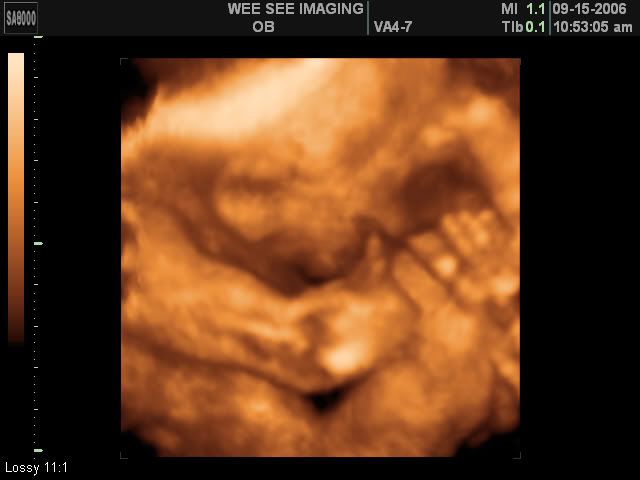

Victoria Rose Kelly

Date Due: December 15, 2006